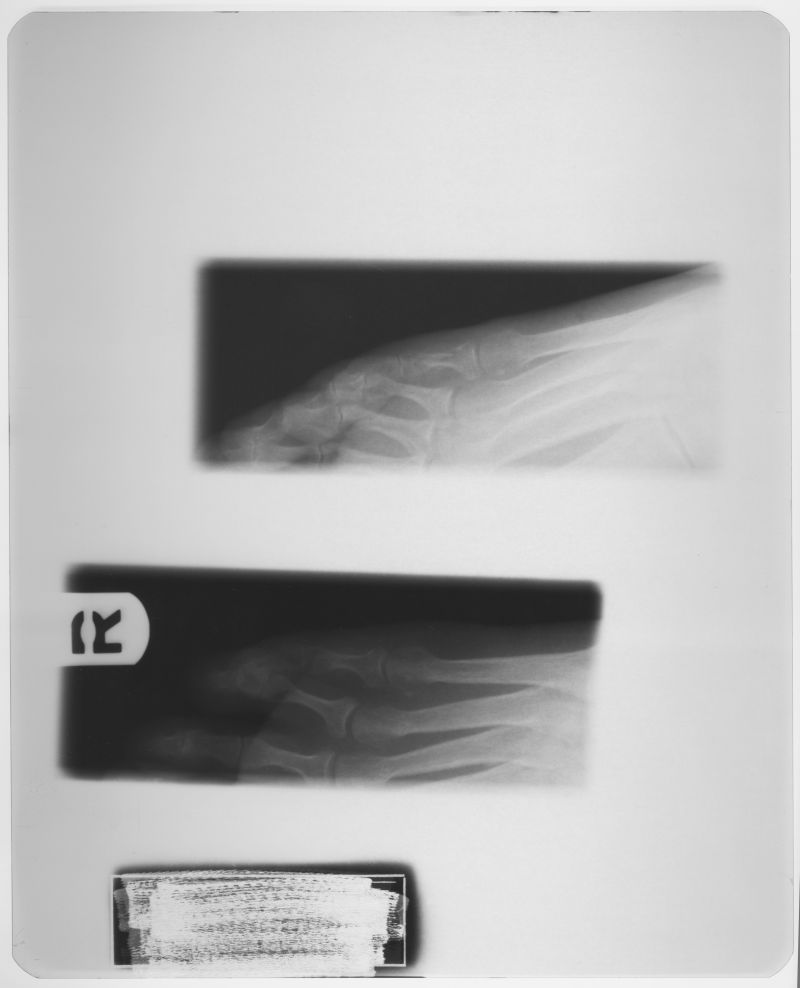

X射线是由于原子中的电子在能量相差悬殊的两个能级之间的跃迁而产生的粒子流,是波长介于紫外线和γ射线 之间的电磁波。其波长很短约介于0.01~100埃之间。由德国物理学家W.K.伦琴于1895年发现,故又称伦琴射线。

X射线是由于原子中的电子在能量相差悬殊的两个能级之间的跃迁而产生的粒子流,是波长介于紫外线和γ射线 之间的电磁波。其波长很短约介于0.01~100埃之间。由德国物理学家W.K.伦琴于1895年发现,故又称伦琴射线。